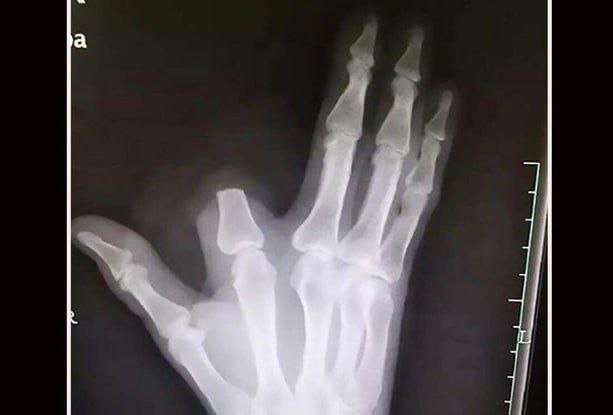

История произошла в Китае: 60-летний фермер из провинции Чжэцзян, работая в поле, запаниковал после укуса и ампутировал себе указательный палец подручными средствами.

Он перевязал руку и сам добрался до больницы, где врачи сообщили, что опасности не было и операция не требовалась. Мужчина выжил, но палец спасти не удалось — его он оставил на месте происшествия.